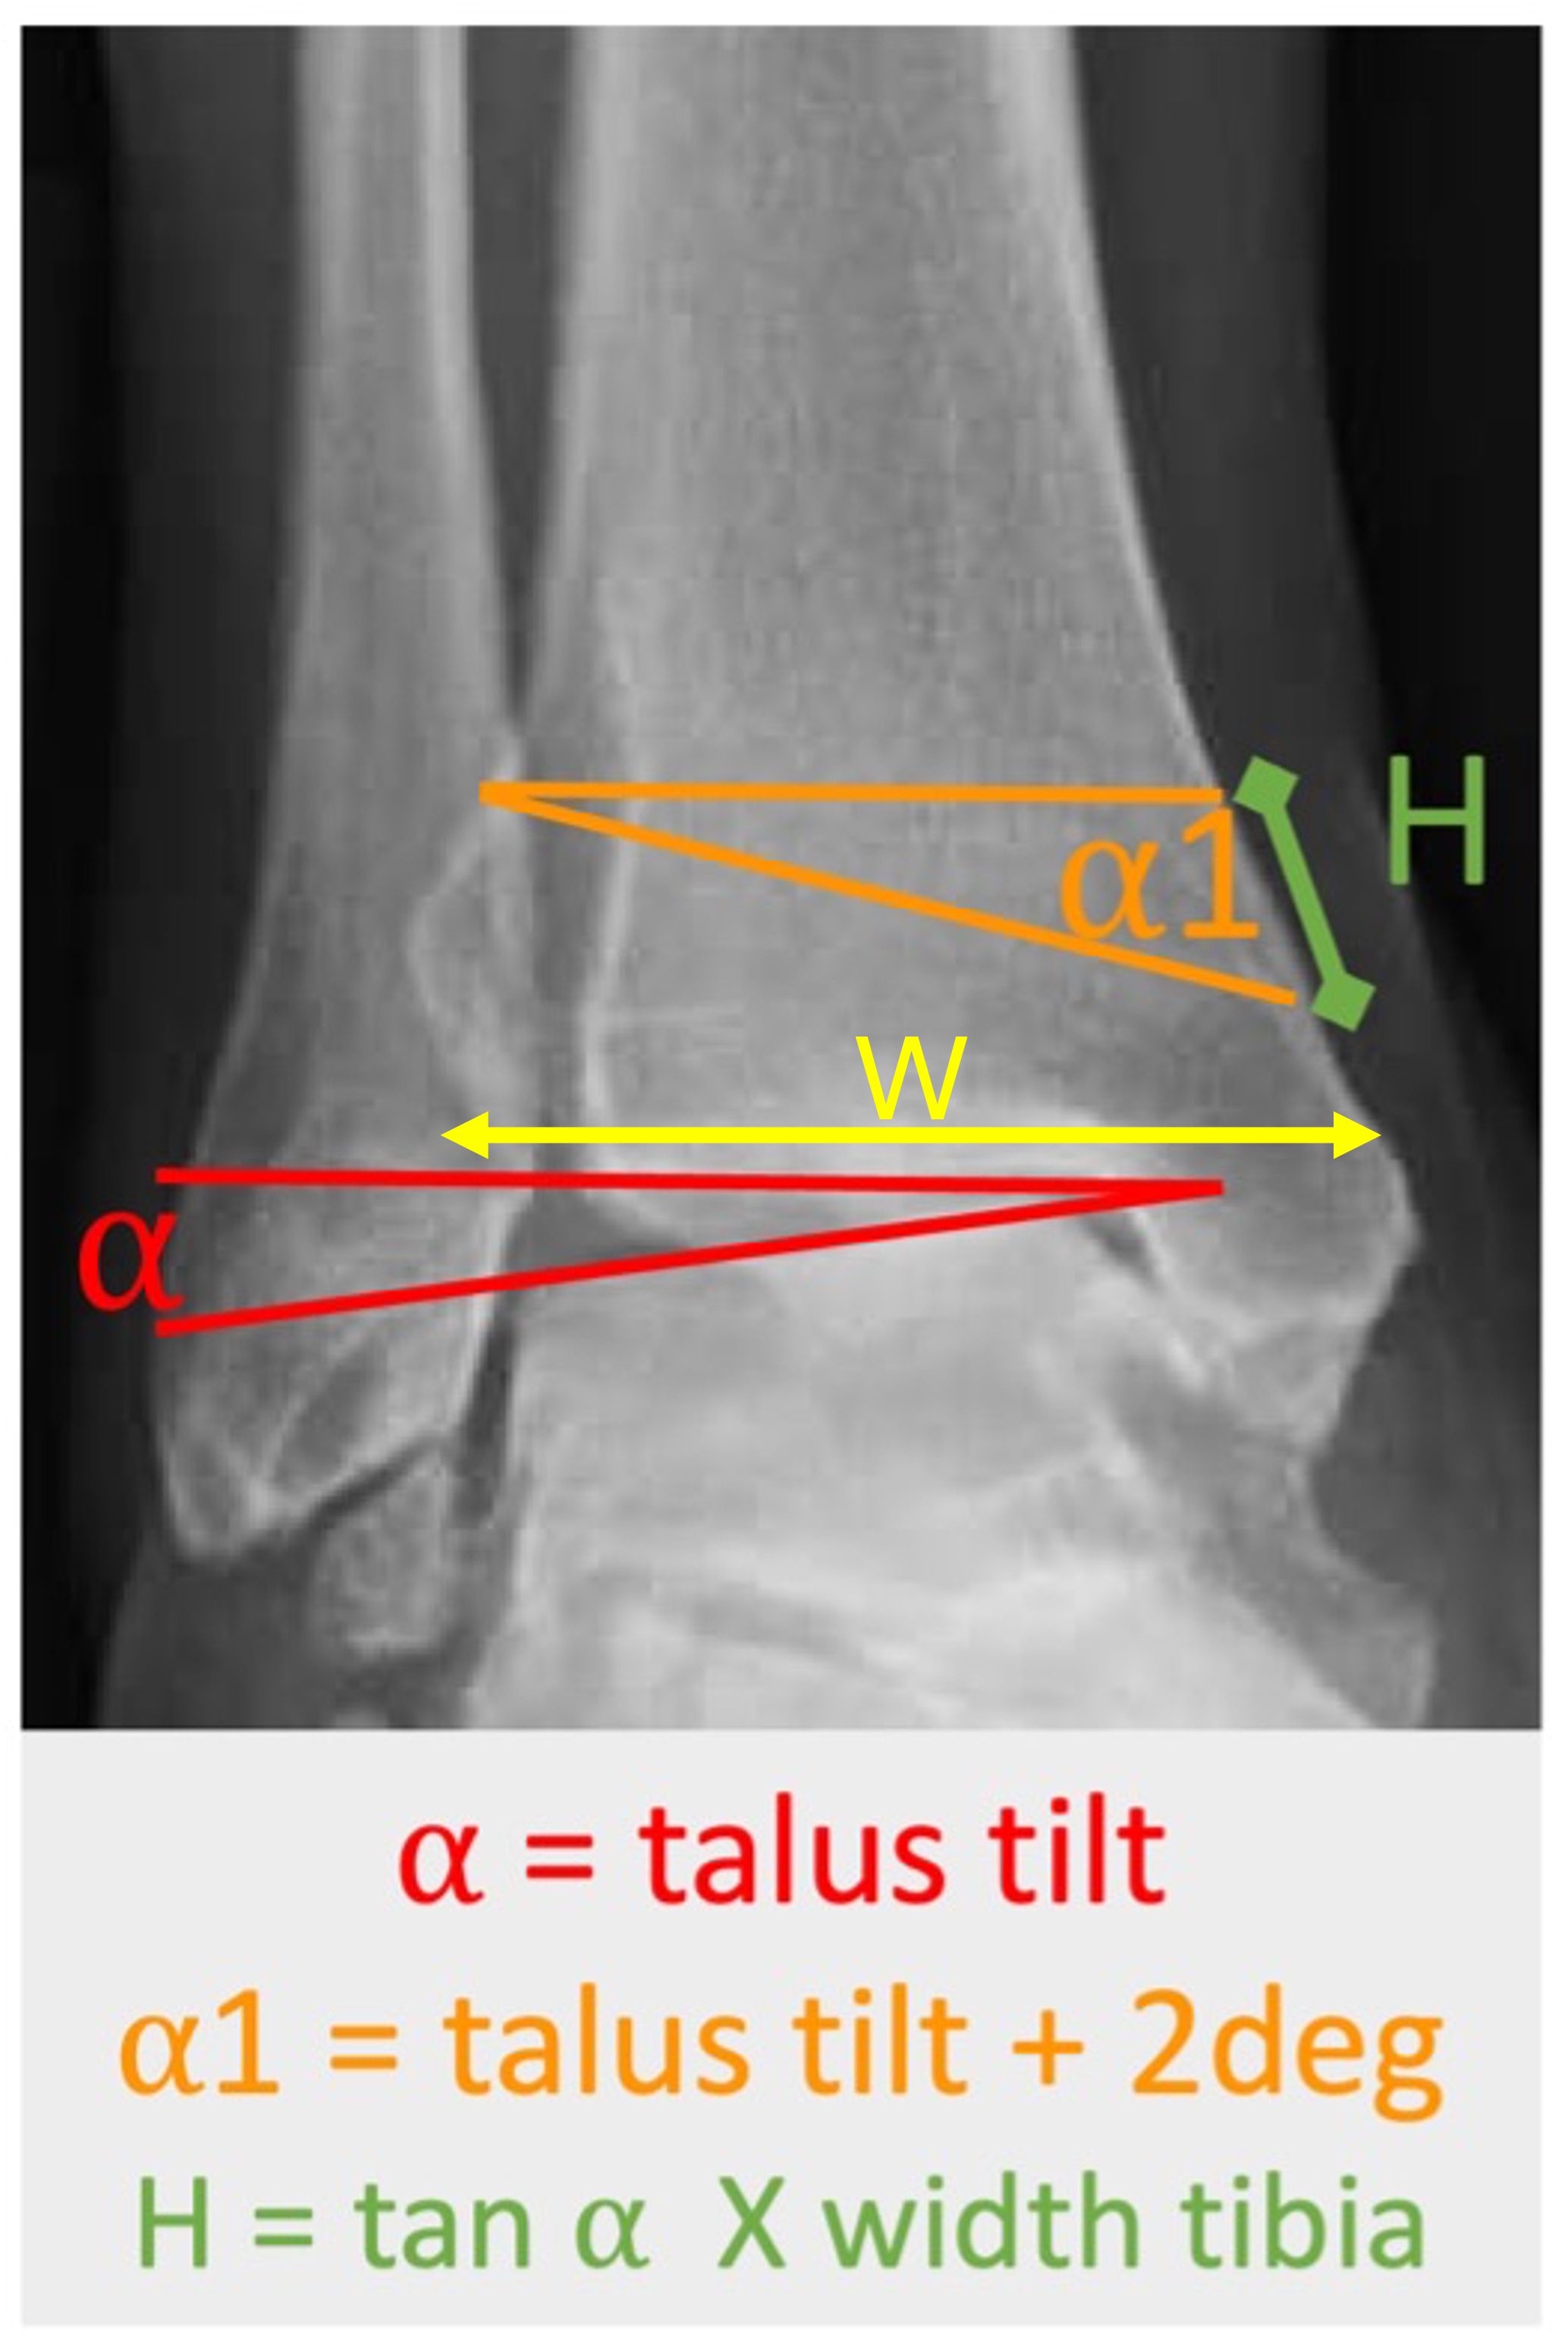

- For calculating the degree of operative correction, the following formula is used to determine the required amount of opening or closing of the osteotomy:

H = tan α₁ x W

-

- H is the height of the wedge

- α₁ is the amount of deformity, incl approx 2°-4° of desired overcorrection

- W is the width of the distal tibia

Figure 6. Calculation of the opening or closing wedge dimensions